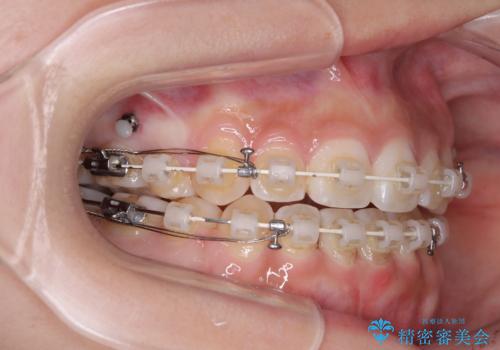

上下非接触の前歯 口元の突出感を改善する抜歯矯正

- 矯正装置

- 審美装置

- 口元の突出感と上下前歯のズレを気にして来院された患者様です。

舌の突出癖により上下の前歯は非接触となっている状態でした。

舌のトレーニングを行わないと上下前歯の接触達成は困難であるため、トレーニングをしっかりと行っていただきながら、治療を進めて行くこととしました。

上下左右の第一小臼歯4本を抜歯し、ワイヤー装置にて矯正治療を行うこととしました。

舌のトレーニングをしっかりと行ってくださり、1年半という非常に短い期間で仕上げることができました。